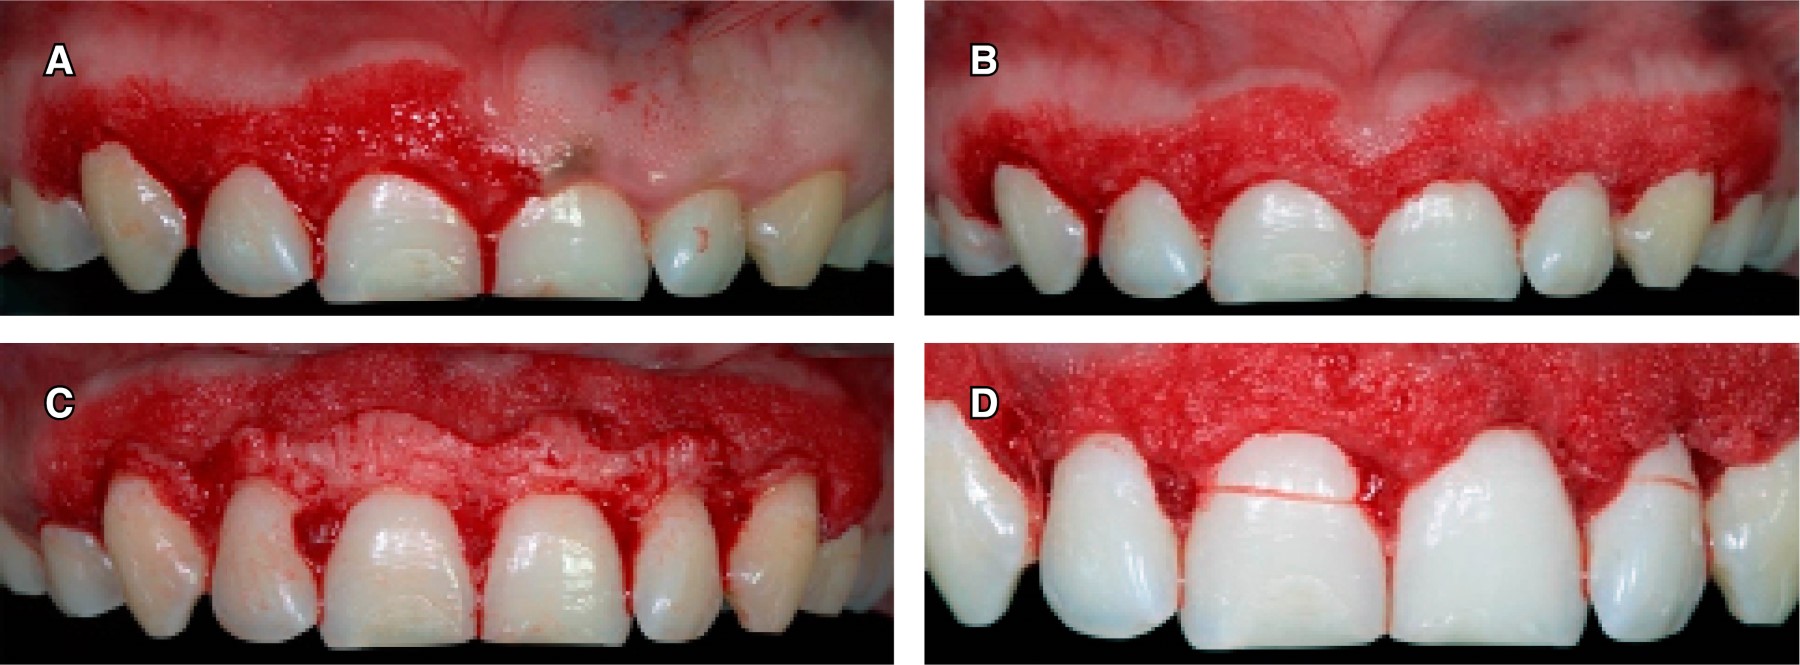

A continuación, con una sonda periodontal se marcó con puntos sangrantes la encía en la zona vestibular (según los datos obtenidos de la CBCT) de todos los dientes a tratar, en seguida se realizó una gingivectomía con una incisión a bisel interno con una hoja de bisturí No. 15c siguiendo el festoneo natural de la encía, y una incisión intracrevicular e incisión interdental; después se realizó una gingivoplastia a bisel interno con bisturí de Kirkland para disminuir el grosor de la encía insertada queratinizada y favorecer­ la posición de encía marginal con respecto a los cuellos de los dientes (Figura 4 A y B). Se elevó un colgajo de espesor total (Figura 4C), se tomaron las medidas de la corona anatómica y se procedió a medir de la distancia de la cresta ósea a la UCE, corona clínica real, corona anatómica con la sonda periodontal (para así poder comparar los resultados obtenidos con CBCT). Por último, el colgajo se reposicionó y suturó con una técnica de sutura suspensoria, con hilo de sutura de ácido poliglicólico (VICRYL) de 4-0 (Figura 4D).